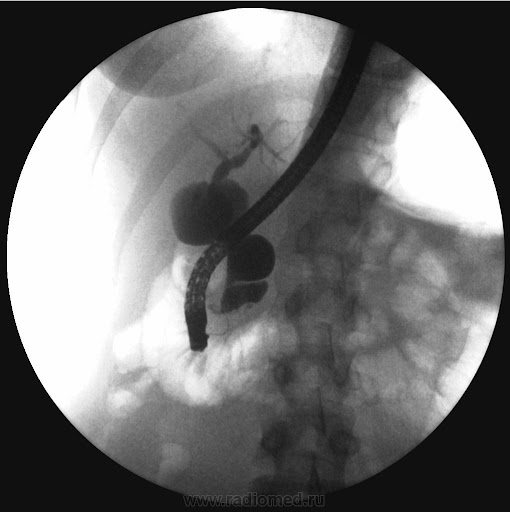

- Сцинтиграфия с технецием-99m. Это «золотой стандарт» диагностики кровоточащего дивертикула. Пациенту вводится безопасный радиофармпрепарат, который накапливается в клетках слизистой желудка. Если в ДМ есть эктопическая желудочная ткань, он станет виден на специальном сканере как «горячий» очаг.

- Диагностическая лапароскопия. В сложных случаях, когда другие методы не дают ясной картины, может быть выполнена лапароскопия. Через небольшой прокол в брюшную полость вводится камера, которая позволяет хирургу напрямую осмотреть кишечник и найти дивертикул. Если он обнаружен, его сразу же удаляют.